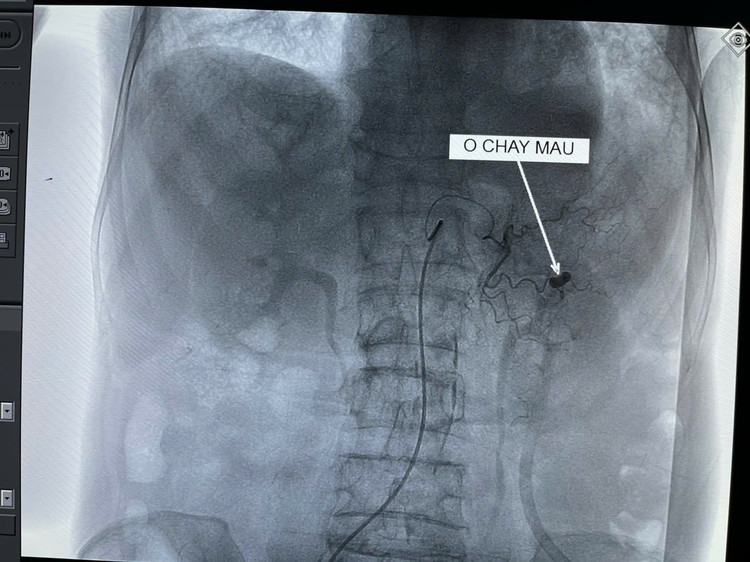

Chảy máu trên phim chụp cắt lớp - Ảnh BVCC

Qua chụp CT tiêm thuốc cản quang và chụp mạch trên máy DSA, thấy được vị trí chảy máu dạ dày tương đối lớn. Các bác sĩ đã tiến hành nút tắc toàn bộ nhánh động mạch chảy máu. Sau can thiệp, chụp kiểm tra lại, hệ thống động mạch không còn điểm chảy máu nào khác trong ống tiêu hóa.